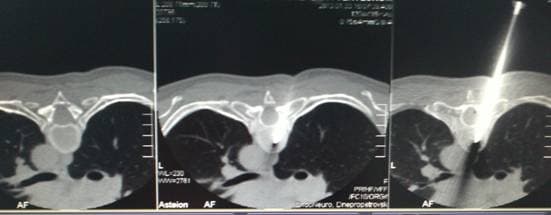

Игла в теле позвонка

Позиционирование иглы в теле позвонка под контролем КТ